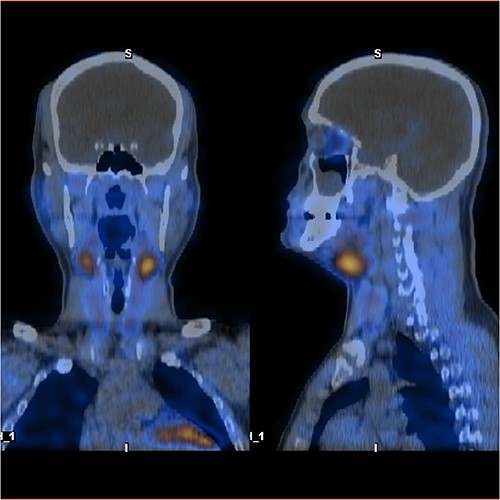

Ultrasound of the neck (Fig. 1), CT and parathyroid sestamibi scan (Fig. 2) failed to localize parathyroid, and all studies showed normal thyroid with no other neck masses or suspicious lymph nodes. Magnetic resonance imaging neck showed no evidence of parathyroid adenoma in the expected typical gland locations or ectopic cervical or upper mediastinum. Therefore, we requested a fluorocholine (FCH) positron emission tomography (PET)/CT (Figs 3 and 4) for localization, which showed normal physiological uptake of the choline in the neck. There was no abnormal focal choline lesion in the thyroid gland or the visualized organs (unremarkable visualized part of the lungs). So, the result was a negative choline scan.